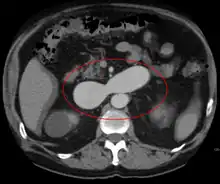

| Micrograph of an arteriovenous malformation in the brain. HPS stain. | |